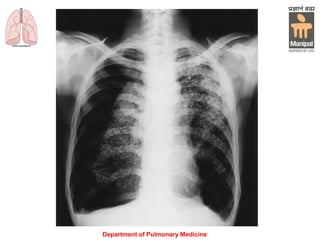

Chest X-ray:

Blunting of the sharp costophrenic angle.

Up to 300 mL of fluid may fail to be seen on a PA

chest radiograph, whereas as little as 150 mL may

be seen on a lateral decubitus view.

A supine film (e.g. in ICU patients) may obscure the

diagnosis because the fluid layers posteriorly.

A pseudotumor occurs when fluid loculates in an

interlobar fissure, a clue to the diagnosis is the

presence of pleural fluid elsewhere and a biconvex

lenticular configuration of the mass.